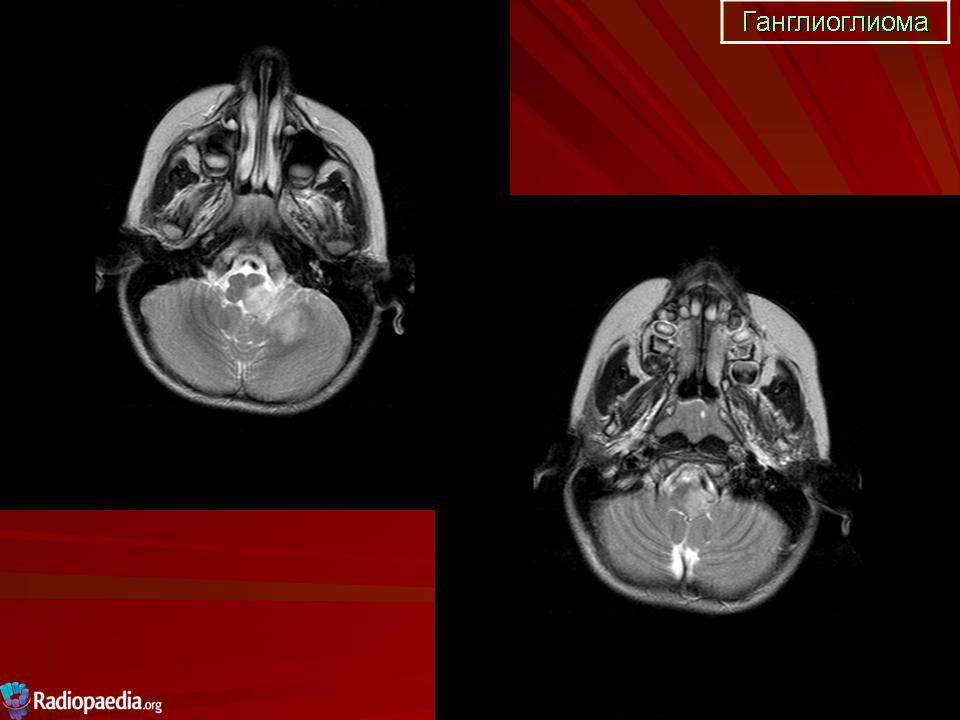

Ганглиоглиома

F. 64 a.  Ganglioglioma

bifrontal supracaloso com componente de neurocitoma central